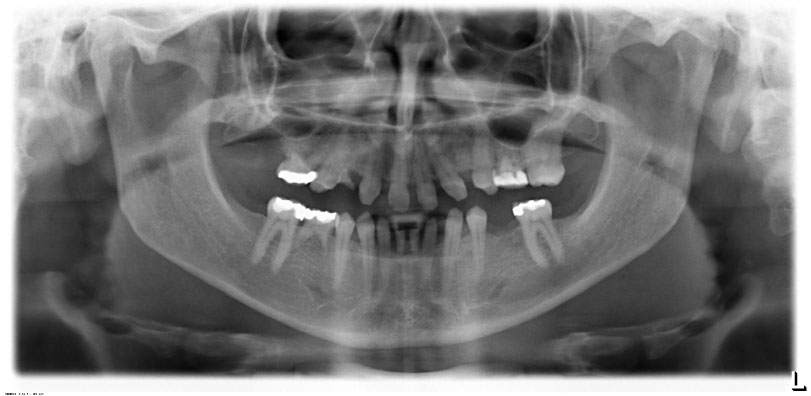

In November 2007, a male patient with ICD10 (K00.0; K07.1) asked for treatment. The diagnosis included craniomandibular malfunction, dysgnathia class III, maxillary retrognathia with horizontal and transverse narrowing of the maxilla, mandibular prognathia with lingual tipping of the mandibular front teeth (Figure 1). Additionally, we diagnosed multiple missing of permanent teeth and hypodontia of deciduous teeth with cones (Figure 2, Figure 3 and Figure 4). Systemically, the patient suffered from platelet deficiency and thrombocytopenia.

Figure 3: Orthopantomography before treatment. View Figure 3

Figure 15: Orthopantomography at the end of treatment. Implant 14 not charged. View Figure 15

We measured good osseointegration > 80 on the Ostell ISQ-scale after this comprehensive corrective osteotomy and the successful healing of the augmentation even for the enossal implants. Facial proportions and the profile expression showed harmonized. The dental situation was satisfying in function as well as in the esthetic aspect (Figures 3). The dentolabial analysis showed good visibility of the teeth in neutral position with cutting edges of 2 mm. Interinzisal lines and middle facial lines assorted well, occlusion and commissure line corresponded. The mandibular-maxillary relation was fixed as central occlusion with maximum intercuspidation Figure 3.